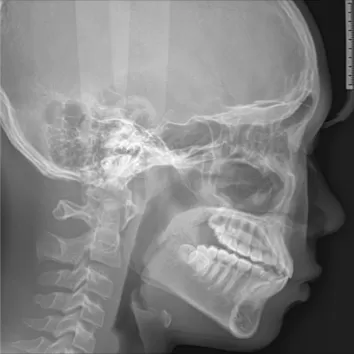

X-rays before treatment

[Panoramic Radiography/Lateral Cephalogram]